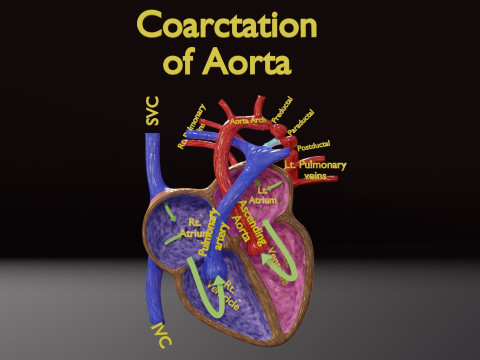

The model meshes include adult circulation versus circulation in Tetralogy of Fallot (TAF), arrow labels and text labels. The blood flow in a patient with Tetralogy of Fallot is outlined in this model. To contrast it to normal blood circulation a separate model of normal circulation is included. The Tetralogy of Fallot (OVER RIDING OF AORTA, PUL STENOSIS, VENTRICULAR SEPTAL DEFECT, RIGHT VENTRICULAR HYPERTROPHY), fossa, ligament teres , venosus, and arteriosus are duly depicted with proper labelling and blood flow directional arrows. Excellent model for teaching, demonstration and knowlegde of human body. The models include both procedural and image textures blend files separately. The texture file include diffuse, roughness and normal png and jpeg based on non overlapping UV maps.